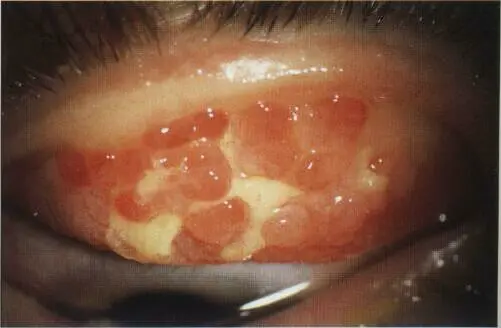

Giant (cobblestone) papillae

Diagnosis: Giant palpebral conjunctivitis

What is the cause: Wearing contact lens, - Chronic allergy